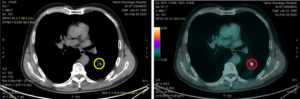

CASE LÂM SÀNG ĐIỀU TRỊ MIỄN DỊCH UNG THƯ PHỔI DI CĂN NÃO TẠI BỆNH VIỆN BẠCH MAI

CASE LÂM SÀNG ĐIỀU TRỊ MIỄN DỊCH UNG THƯ PHỔI DI CĂN NÃO TẠI BỆNH VIỆN BẠCH MAI GS.TS. Mai Trọng Khoa, BSNT Nguyễn Đức Thịnh, PGS.TS. Phạm Cẩm Phương, PGS.TS. Phạm Văn Thái, Trung tâm Y học hạt nhân và Ung bướu, Bệnh viện Bạch Mai Ung thư...